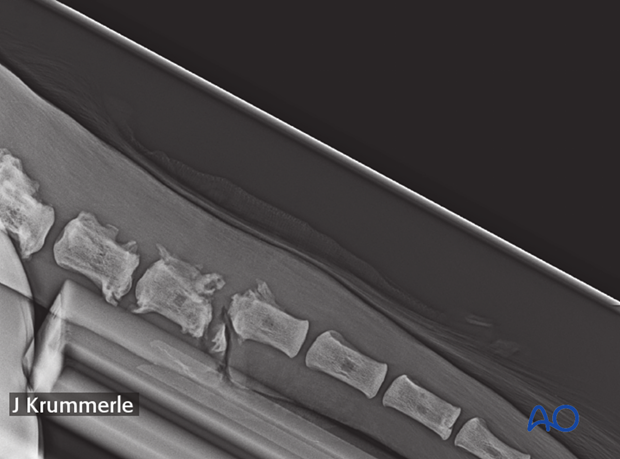

Lateral or oblique lateral radiographs confirm the presence of a vertebral fracture.

22-year-old warm blood with an open infected fracture in Co7.

Lytic and proliferative lesion of the coccygeal vertebra.